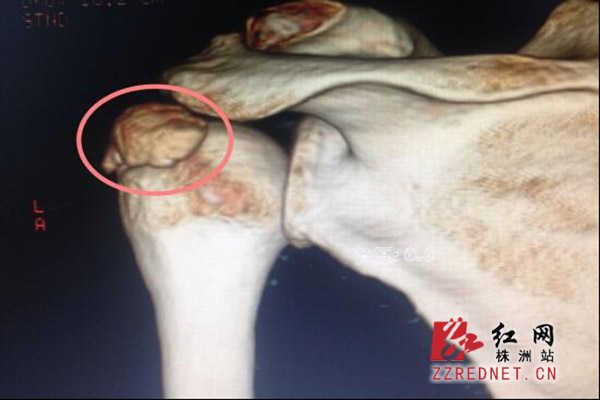

X片上显示的异常“骨块”

突然一下,肩膀疼痛剧烈任女士是益阳南县人,在株洲一家超市打工,大概半个月前,突然出现左肩膀剧烈疼痛,抬不起来,随即前往附近医院就医,“做了磁共振,并没有发现异常,也扎了银针,疼痛也没有减轻。”随后,任女士来到市伤科医院,“患者左侧肩关节各个方向活动受限,之前的医生诊断为肩周炎,一般肩周炎的疼痛是渐进,缓慢加重的,而患者的疼痛是突然产生且剧烈。”李康贵称任女士之前的核磁上也没有肩周炎的影像表现,可排除肩周炎,“患者的年龄,正好又在超市工作,类似于家庭主妇,正好处于一种叫钙化性肌腱炎的好发年龄段,该症好发于30—50岁的家庭妇女,中年女性患者约占所有发病人群的45%。”肩膀多块“骨头”,一般可自愈李康贵介绍,钙化性肌腱炎很特殊,在核磁上并不明显,“如果不是很有经验的医生,是看不出来的。而在X片和CT上则看得较清楚。”记者在X片上看到,在任女士左肩袖位置有一个明显的异常骨块(软骨),“钙质在肩袖位置沉积,随之产生剧烈疼痛。”

“钙化性肌腱炎病因不明,大致分为三期,钙化前期、钙化期、钙化后期,一般在后两期会出现疼痛,目前查阅文献最小的患者为一名3岁女孩。”肩肘科主任,副主任医师齐隆辉表示钙化性肌腱炎,沉积的“骨块”较小时,一般可以被吸收,可自愈。“而患者的骨块比较大,又剧烈疼痛,通过自己吸收,怕是时间很长,只能通过手术予以摘除。”李康贵称手术后,任女士的疼痛立马解除,目前已康复出院。”所以,肩膀疼痛并不都是肩周炎惹的祸,如相关部位出现麻木、疼痛,建议到正规医院专科就医,及时发现问题,及时解决。“李康贵表示。